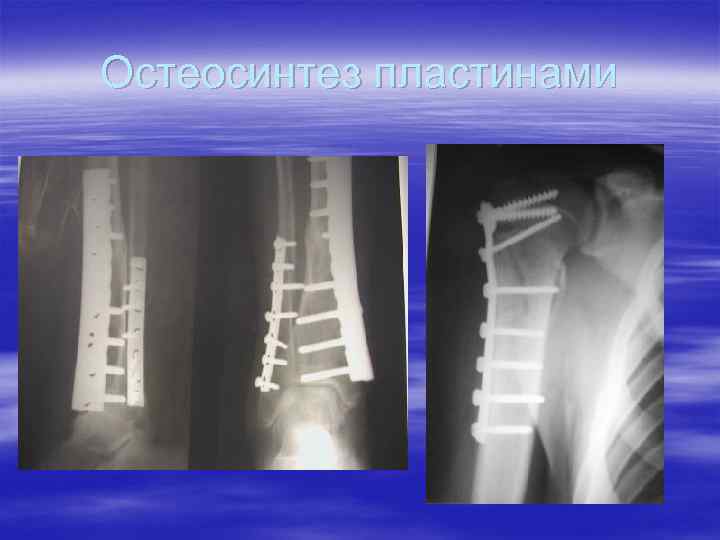

Остеосинтез пластинами

Остеосинтез мыщелков большеберцовой кости Numelock 2

Остеосинтез пластиной Numelock 2 (Stryker)